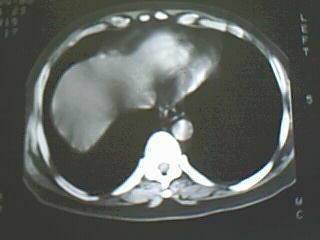

支持:左肺上叶中央型肺癌伴阻塞性肺炎,建议支气管镜

考虑左肺上叶中央型肺癌伴阻塞性肺炎可能。建议支气管镜检查排除结核。

支持:左肺上叶中央型肺癌伴阻塞性肺炎可能性大,建议气管镜 。

考虑左侧中央型肺癌并阻塞性肺炎,建议支纤镜检